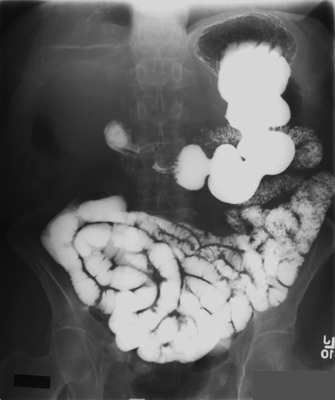

Figure: Normal Small Bowel